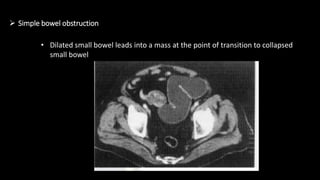

 Simple bowel obstruction

• Dilated small bowel leads into a mass at the point of transition to collapsed

small bowel